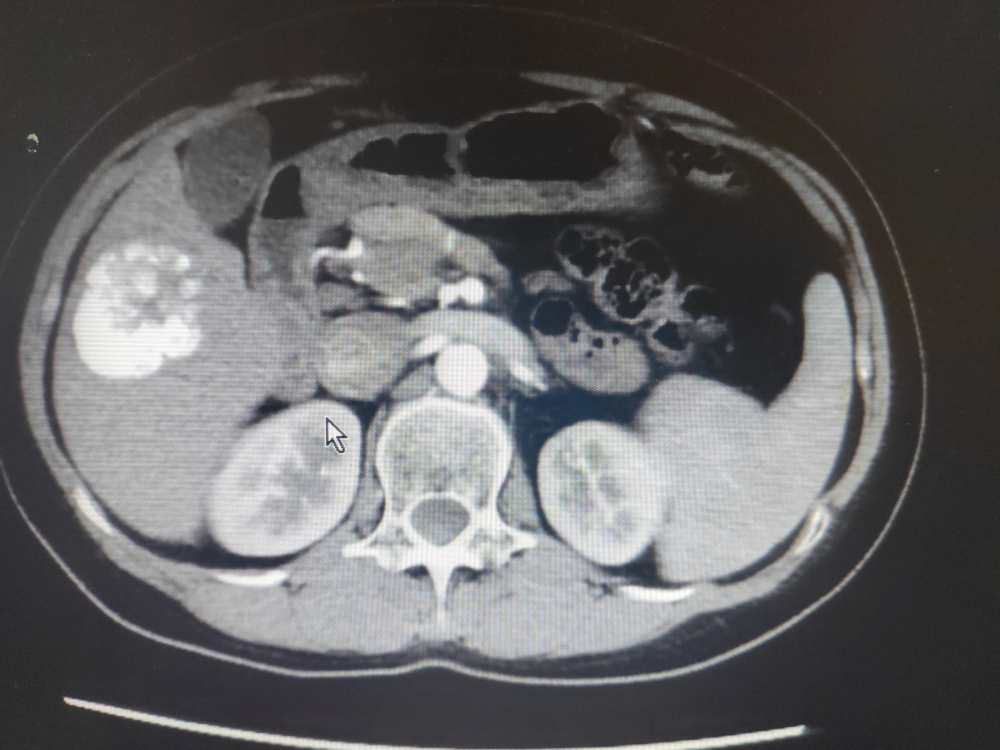

2023年4月15日上腹部增強CT